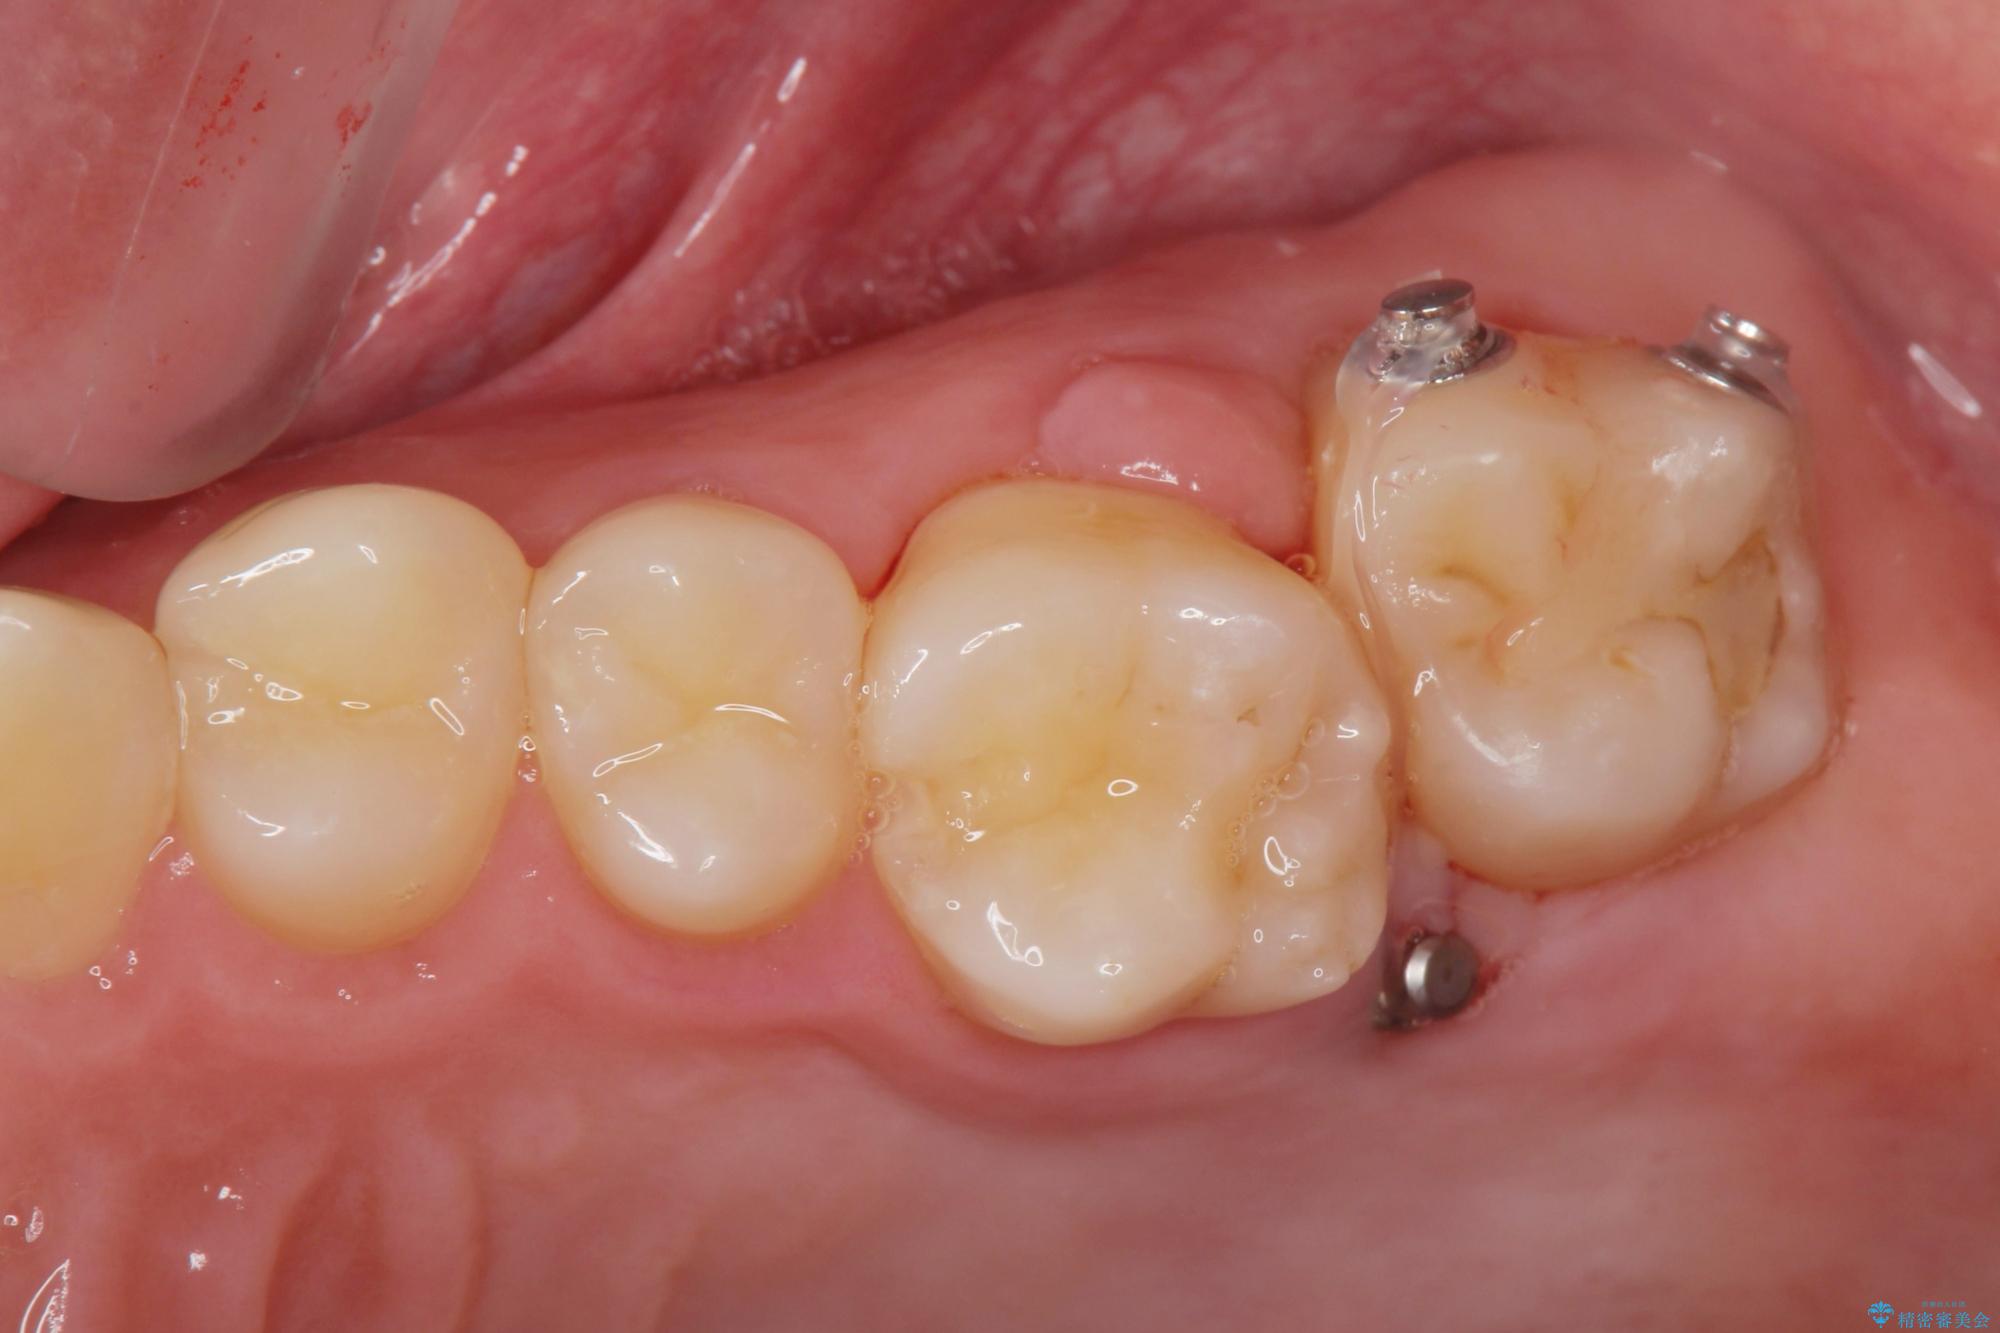

左上の奥歯がシザーバイトがありました。

部分矯正を行いシザーバイトを改善した後、インビザラインで歯列を整えました。

シザーバイトは歯と歯が噛み合っていないのでしっかり噛めるように処置をする必要があります。